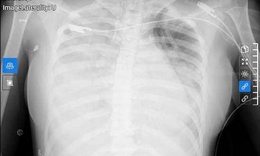

Hậu COVID-19, 2 bệnh nhân phổi đông đặc, có nhiều ổ cặn

Y tế - 29/12/2022 19:15SKĐS - 2 bệnh nhân cao tuổi đều nhập BVĐK Đức Giang (Hà Nội) do đầu đau, tức ngực. Chụp X - Quang cho thấy, bệnh nhân có nhiều dịch màng phổi.